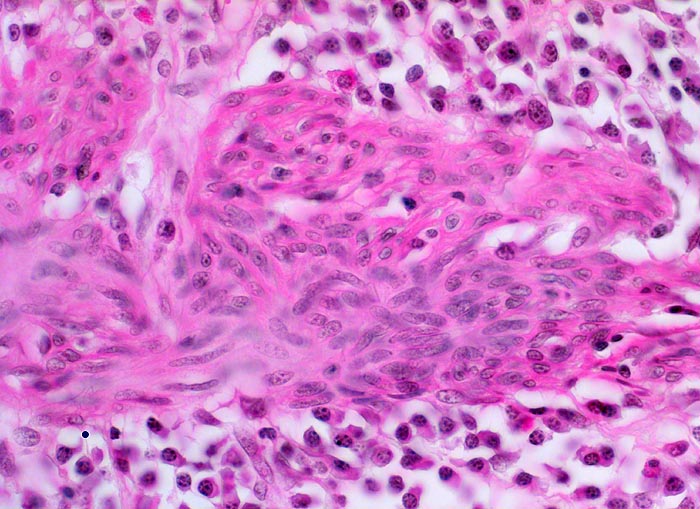

Colitis ulcerosa

In der Bildmitte ist die glatte Muskulatur der Lamina muscularis mucosae erkennbar. Zu beiden Seiten der Muskulatur finden sich dichte Infiltrate von Plasmazellen, vereinzelte eosinophile Granulozyten und Lymphozyten.

Das normale Entzündungsinfiltrat der Lamina propria enthält eine Mischung von Lymphozyten, Plasmazellen und eosinophilen Granulozyten. Der Nachweis von neutrophilen Granulozyten ist pathologisch und spricht für eine aktive Entzündung. Normalerweise ist das Entzündungsinfiltrat lumenwärts verdichtet. Bei entzündlichen Darmerkrankungen besteht ein diffuses dichtes Infiltrat, das auffallend reich ist an Plasmazellen und oft auch eosinophilen Granulozyten. Je nach Aktivitätsgrad der Entzündung sind unterschiedliche Mengen von neutrophilen Granulozyten beigemischt. Bei der Colitis ulcerosa ist die Entzündung meist auf die Mucosa beschränkt, kann in schweren Fällen (wie hier) aber auch auf die Submukosa übergreifen.